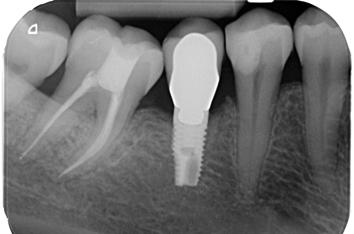

5. ábra: Egyéves kontrollröntgen. – 6. ábra: Kiindulási felvétel. A mesiális irányba dőlt alsó első nagyőrlőfogat irreverzibilis pulpitissel diagnosztizáltuk, amely vélelmezhetően a disztális oldalán található parodontális lézióból indult ki. – 7. ábra: A posztoperatív felvételen látható, hogy a hozzáférési nyílás kialakítása a fog tengelyállásának megfelelő szögben történt.